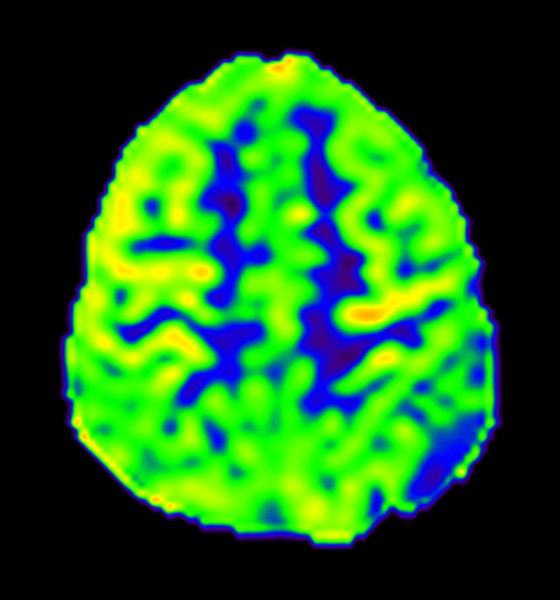

入院后,医院为她进行了详尽的颅脑MRI增强及头颅CT薄扫检查,结果显示其病变位于左侧顶上小叶,病变对脑组织压迫明显(病变周围脑组织CBF灌注明显降低、较对侧脑回体积明显减小),且与左侧大脑上静脉紧密相关,动态视频脑电图分析进一步提示病灶周围脑组织存在异常放电。

术前ASL图像(显示病变周围脑组织灌注降低)

术前MRI提示左侧中央后回较对侧稍小。